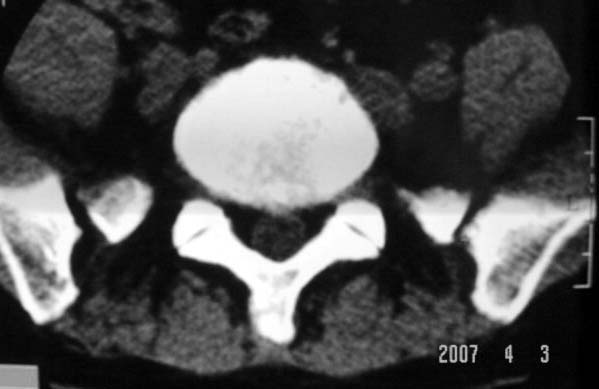

行腰椎间盘检查时,发现左侧髂骨后缘一类圆形低密度影,ct值约负43hu。

左侧髂骨囊状低密度影,边缘硬化.考虑:髂骨骨纤维异常增殖症.

左侧髂骨后缘类圆形骨质缺损区 ,边缘清晰,我考虑为骨囊肿可能性大.